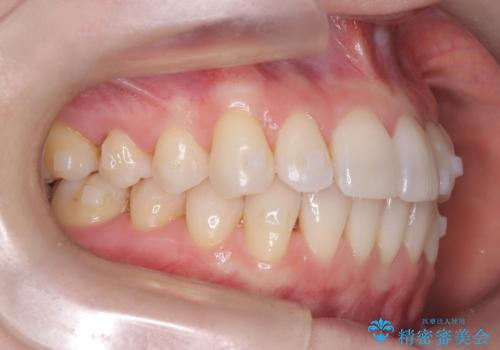

矯正後の後戻りで前歯にガタツキができてしまった インビザラインで改善

- 子どものときにワイヤー矯正をしていたが、後戻りによって前歯のガタツキが気になってきたとのことで来院されました。

アライナー矯正希望だったため、インビザラインによる治療を行いました。